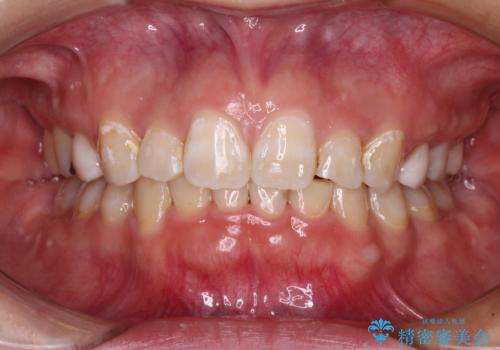

- 咬み合わせと、前歯のデコボコや八重歯、飛び出した口元を気にして来院された患者様です。

上顎は歯列不正が強く、右側臼歯部の咬み合わせは歯1本分ずれている状態でした。

補助装置を用いて奥歯の咬み合わせを改善しながら歯列を後方に移動させ、上下左右第一小臼歯を4本抜歯することで八重歯や口元の突出感を改善することとしました。

奥歯の咬み合わせの不正が顕著であったため、表側のワイヤー装置を選択して矯正治療を行うこととしました。